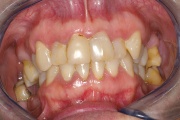

Sjörgeni sündroomist tingitud suukuivus